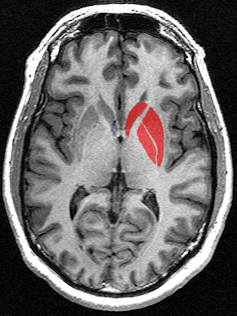

Plusieurs fois évoqué au cours de l’ouvrage, le striatum va devenir, à partir de la page 185, la clé pour expliquer notre incapacité à réformer le système. Plus exactement, le striatum, cette partie de notre cerveau qui commande la dopamine, la molécule du plaisir, est en fait la clé de compréhension du capitalisme.

Si celui-ci s’est développé de cette manière, c’est grâce à ou à cause du striatum qui « nous pousse à agir de manière irrépressible en passant au-dessus de notre intelligence » (page 185).